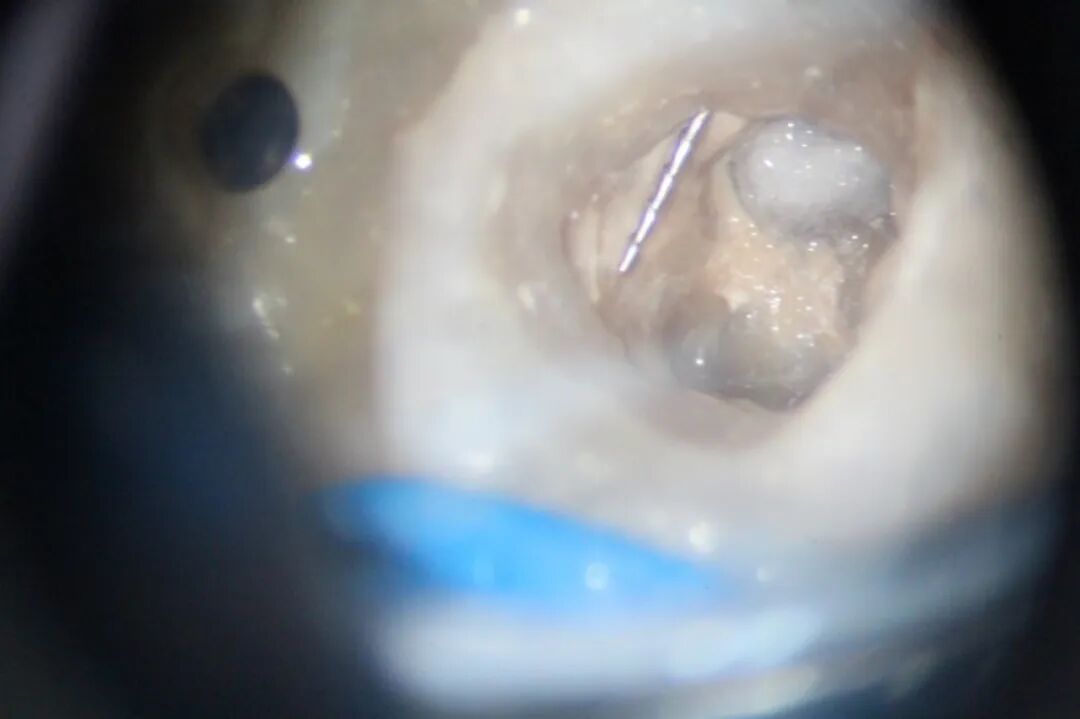

5、 显微超声技术。是目前应用最普遍也是行之有效的方法,成功率较高。但仍存在一系列弊端,如去除牙本质较多,可能发生穿孔或将器械推出根尖孔,使用过程中温度升高,可能导致器械发生二次分离等。

▲从根管内取出“断针”

医生提醒,确保疗效是根管治疗的首要目的,如果为了强行取“断针”,反而造成更大的伤害,那就得不偿失了。如评估不需取出“断针”,可采取激光消毒的方法,杀灭细菌、防止感染。

作为深圳市属公立口腔专科医院,我院已配备多种器械分离处理专用设备,为多位转诊患者成功取出“断针”。

▲我院器械分离处理设备配置齐全

▲我院为多位转诊患者成功取出“断针”